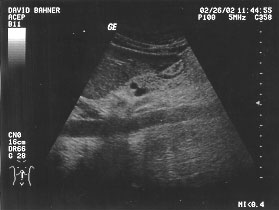

Gallbladder (unlabeled)